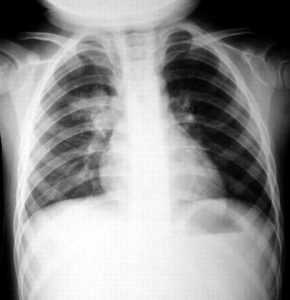

X 線胸片檢查

通過給病人進行X線胸片檢查,可以直接了解肺部的變化,這是診斷肺炎的重要手段,雖然通過血象和X線胸片可以診斷肺炎,但肺炎是由什麼病原體引起的,是由細菌,還是由病毒,支原體,真菌等引起的,細菌的種類是什麼,上述兩項檢查就不能告訴我們了,只能合理的取患者的痰、血做培養有可能真正找出致病菌。醫生們就可以有針對性的採用對病原體敏感的藥物進行治療了。血常規、胸部X線檢查及痰的檢查是患有肺炎病人進行的最基本檢查,除此之外還有胸部CT檢查(醫學上稱為電子計算機斷層掃描)。但是如果病人在同一部位反覆發生肺炎或X線胸片上有其它可疑的病變,而一般檢查難以明確診斷時,就需要進行胸部CT檢查或其他更進一步的檢查。

對於肺炎的診斷,胸腔X光照射肺部出現浸潤現象是診斷肺炎的黃金標準,支持性的診斷方法則是由病患的痰液或血液進行微生物的培養。當懷疑有肺炎時,通常會進行血液檢查:完全血球計數可以顯示出嗜中性球的增生(除了某些免疫不全或嗜中性球減少症的病患之外)。若病情發展為敗血症,病患的腎功能可能有下降的情形。在離子的測定方面,通常由於肺炎的肺部組織釋出抗尿激素而導致納離子的降低。

確定肺炎診斷首先必須把肺炎與上呼吸道感染和下呼吸道感染區別開來。呼吸道感染雖然有咳嗽、咳痰和發熱等症狀,但各有其特點,上下呼吸道感染無肺實質浸潤,胸部X線檢查可鑑別。